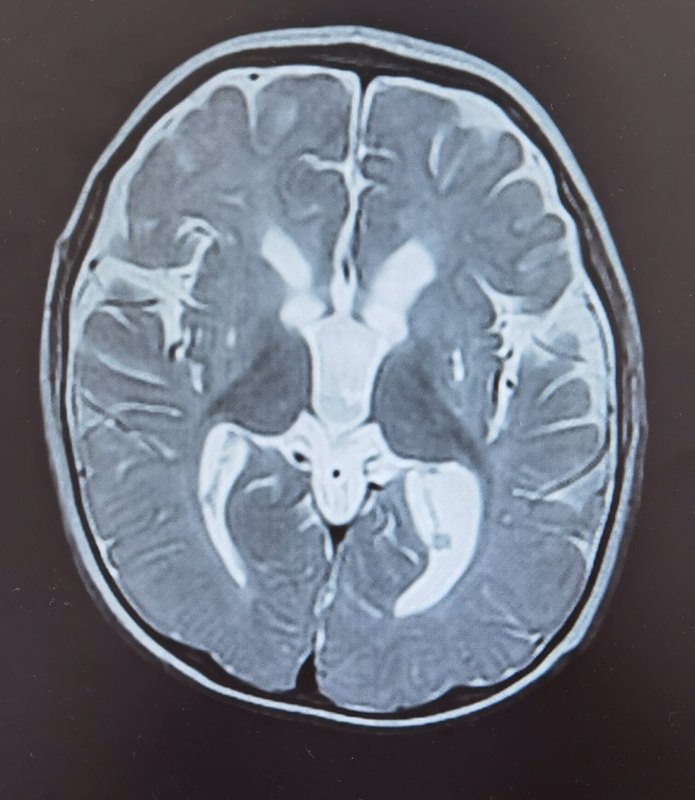

嬰兒癲癇性痙攣發(fā)作綜合征(ISs)是年齡依賴性癲癇性腦病,不僅發(fā)作控制困難,而且常導(dǎo)致發(fā)育停滯或倒退,導(dǎo)致不良預(yù)后。近年來的研究進(jìn)展提示,合理化的病因診斷、精心調(diào)整抗發(fā)作治療方案、早期發(fā)育評(píng)估和康復(fù)介入,半數(shù)以上的患兒可以控制發(fā)作、改善腦電、促進(jìn)發(fā)育?;純耗袑殻?月齡。自幼發(fā)育落后,至今仍豎頭不穩(wěn)、不會(huì)翻身和獨(dú)坐、不會(huì)主動(dòng)抓物,對(duì)視和互動(dòng)少,極少能逗笑。生后5個(gè)月開始出現(xiàn)醒后發(fā)作性擁抱樣動(dòng)作,每日2~3次,每次10~20幾下。寶寶系足月兒,生后有缺氧,新生兒1分鐘阿氏評(píng)分2分,NICU住院治療2周余。體格檢查:表情淡漠,視聽反應(yīng)欠佳,運(yùn)動(dòng)認(rèn)知符合2個(gè)月水平,右側(cè)為主四肢肌張力增高伴不隨意運(yùn)動(dòng),腱反射亢進(jìn)。顱腦磁共振檢查:顯示多發(fā)性腦軟化灶伴局部萎縮膠質(zhì)增生腦電圖監(jiān)測(cè)到醒睡各期多灶性放電,睡眠期高度失律。初步診斷:1.癲痛(痙攣發(fā)作,嬰兒痙攣癥,結(jié)構(gòu)性);2.腦癱高危兒。治療經(jīng)過:初診后收住院擬激素治療,但因感染肺炎只能抗癲癇發(fā)作藥物治療,先后給予氨己烯酸、妥泰、硝西泮、德巴金等,發(fā)作減輕,每天3-4串,每串?dāng)?shù)1下至8左右不等。發(fā)病2個(gè)月后住院激素治療,仍每日單下發(fā)作6-7次,精神狀態(tài)見好,能逗笑和追視,進(jìn)一步調(diào)整治療方案,終于2022年12月24日至今未再發(fā)作,認(rèn)知反應(yīng)改善。目前指導(dǎo)下家庭康復(fù)中。復(fù)查2小時(shí)視頻腦電圖顯示高度失律消失僅有睡眠期前頭部偶發(fā)性尖慢波。希望通過這個(gè)案例增加癲癇治療的信心,只要依從-堅(jiān)持-耐心,總歸能夠增加可能控制的機(jī)會(huì)。治療癲癇需要醫(yī)患攜手共同努力!更多癲癇相關(guān)信息請(qǐng)關(guān)注我的科普公眾號(hào),也歡迎大家問診和就診。